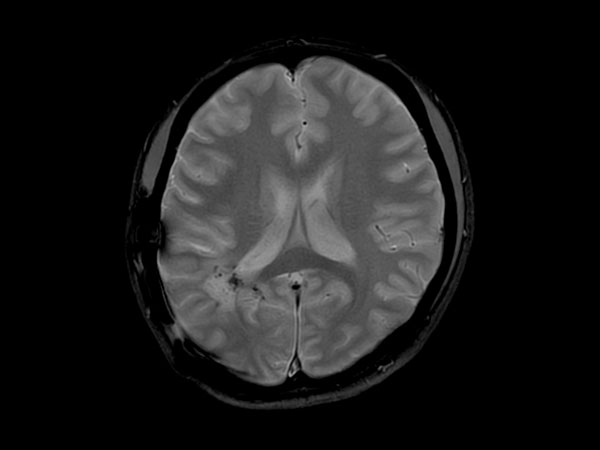

Patient with a glioblastoma recurrence. Glioblastoma was surgically removed 5 month ago. The gadolinium enhancement was first thought to be the enhancement of choroid plexus. However this was diagnosed recurrence of glioblastoma due to the high APT value.

Axial T2w TSE